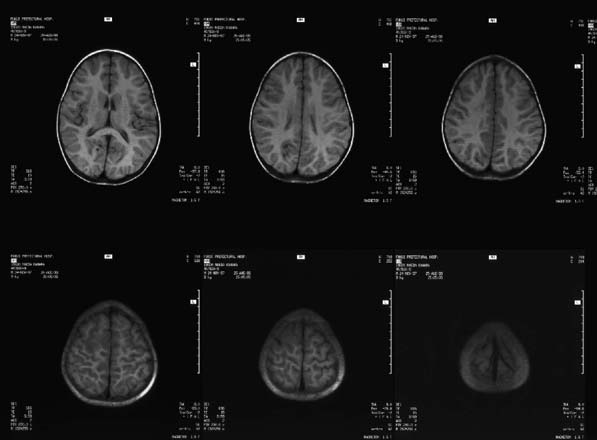

CaseHE02

- Age/Sex: 3 M

- Chief Complaint: けいれん発作重積状態

- Clinical Course:

- Lab. Data:

- Images:

- MR T1 (a)

- MR T1 (b)

- MR T2 (a)

- MR T2 (b)

- Tc-99m ECD Aug/27

- Tc-99m ECD Aug/31